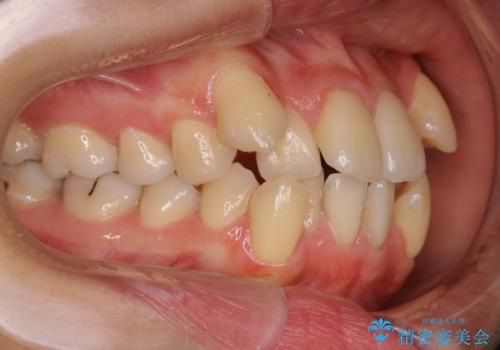

八重歯がスッキリ 抜歯ワイヤー矯正

- 以前からコンプレックスだった八重歯の治療を主訴にご来院されました。

奥歯の上下のズレ等は軽度で、必要なスペースと抜歯により作られるスペースがほぼ等量だったため治療の単純化が計れ、大きな移動・見た目の劇的な変化に対して比較的早期での治療完了となりました。

叢生の度合いが重く、抜歯が必要なケース。八重歯の部分以外には大きな問題は認められなかったため、劇的変化が起こる治療でも比較的短期間で終了することができました。